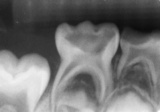

Συχνά σε νεογιλά δόντια που είναι αρκετά χαλασμένα η τερηδόνα (μικροβιακή μόλυνση) φτάνει ως το νεύρο του δοντιού. Σε αυτές τις περιπτώσεις και ανάλογα με την «έκταση» της μόλυνσης υπάρχουν δύο επιλογές, αυτή της πολφοτομής (μισής απονεύρωσης) και αυτή της ενδοδοντικής θεραπείας (πλήρους απονεύρωσης) του νεογιλού δοντιού.

Στην πολφοτομή το πάνω μέρος (μολυσμένο) του νεύρου αφαιρείται και το μέρος του νεύρου των ριζών, μετά την τοποθέτηση κάποιων φαρμάκων, διατηρείται μέχρι φυσιολογικά αυτές να απορροφηθούν (λιώσουν) καθώς φυτρώνει το μόνιμο δόντι.